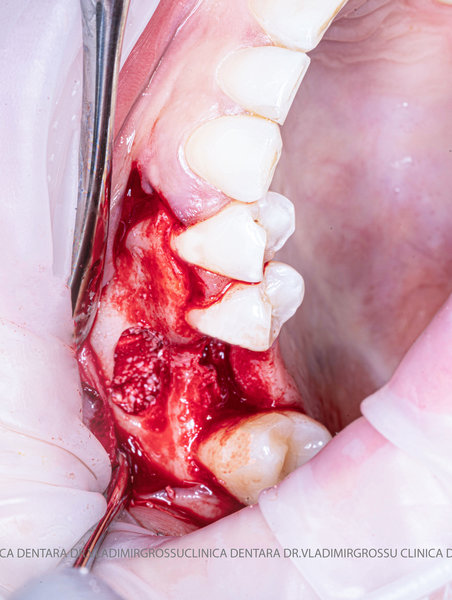

După extracția dentară, în intervalul de 6-12 luni, osul alveolar suferă un proces natural de remodelare, ceea ce conduce la scăderea volumului osos prin rezorbție. De aceea, inserția implantului dentar este ideală imediat după extracție sau, cel târziu, în primele 3-4 luni după aceasta.Scopul procedurilor de adiție osoasă este refacerea fundației osoase necesare pentru stabilizarea corectă a implantului dentar. Pentru ca un implant să reziste în timp la forțele masticatorii, este nevoie de o bază osoasă solidă și sănătoasă.

Cele mai utilizate patru categorii de materiale, în funcție de origine, sunt:

- Autogrefe — os propriu, recoltat de la pacient;

- Alogrefe — os uman prelucrat, recoltat de la donatori vii sau decedați;

- Xenogrefe — os de origine bovină;

- Materiale osteoplastice sintetice — cu avantaje și limitări specifice.

Un element esențial în procedura de aditie osoasă este utilizarea membranelor biologice, care izolează materialul osos de țesuturile moi (gingie) pe durata procesului de vindecare. Cele mai recomandate sunt membranele resorbabile din colagen sau pericard.